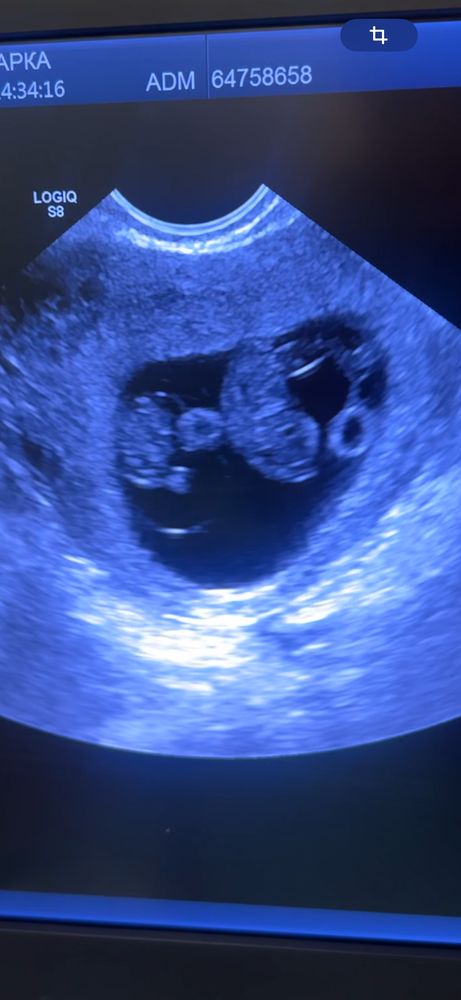

за неделю ребятишки выросли аж на 10 мм

и да, ура! нам подтвердили моно-ди!